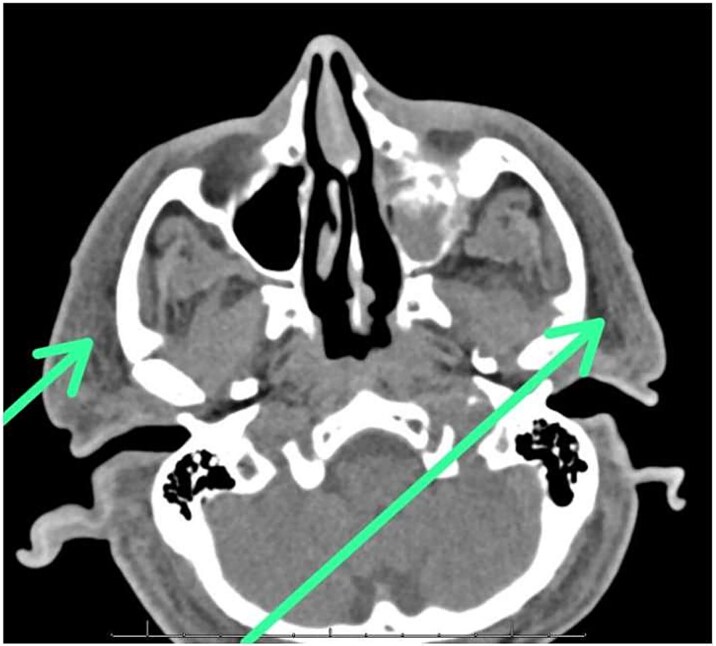

Case presentation: We present the case of a 70-year-old male who developed facial necrotizing fasciitis with rapid systemic progression. He initially presented to the emergency department with acute tenderness and swelling of the right ear. CT imaging revealed extensive edema and swelling in the subcutaneous fat of the face, scalp, and neck, most prominently involving the right external ear. Despite aggressive supportive measures-including ventilatory, cardiovascular, and renal support-the infection progressed to severe multi-organ failure, ultimately resulting in death.